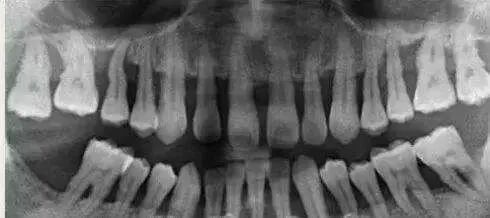

1、牙龈炎仅仅是龈组织的炎症,出现红肿、点斑消失;而牙周炎不仅出现牙龈的炎症,还包括整个牙周组织的炎症。2、牙龈炎没有骨的破坏,所以X线片上没有骨吸收的情况。而牙周炎X线片上可见牙槽嵴的高度降低,呈水平型吸收,也可出现近牙根面的牙槽骨吸收,呈垂直或角形骨吸收,这种骨的吸收,临床上表现为骨下袋。